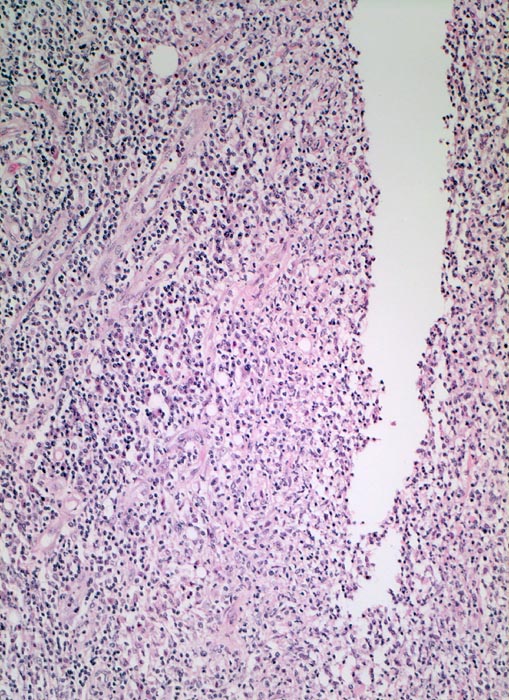

Morbus Crohn: fissurales Ulkus

Spaltförmiges Ulkus gesäumt von entzündlich infiltriertem Granulationsgewebe mit zahlreichen Gefässen.

Bekannter Morbus Crohn. Resektion des terminalen Ileum wegen mechanischem Subileus und enterokutaner Fistelbildung.

Die Vermehrung von Nerven ist typisch bei Morbus Crohn.

100